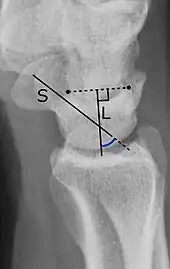

- A line through the long axis of the scaphoid bone.

- A line perpendicular to the distal articular surface of the lunate bone.

It should normally be 30°-60°.[1]